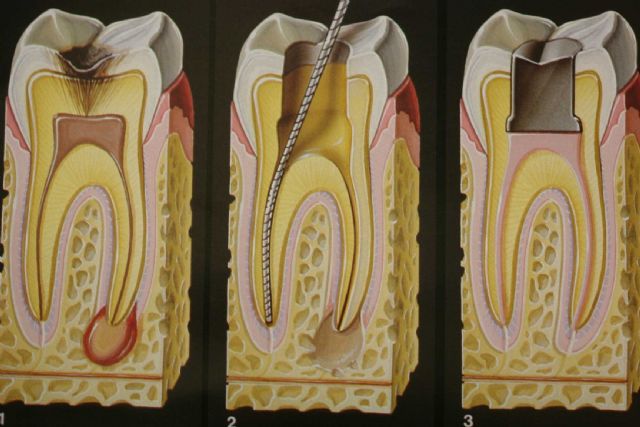

Endodonti (Kanal Tedavisi)

Enfekte olmuş dişleri kurtaran kanal tedavisi. Ağrısız ve konforlu tedavi süreci.